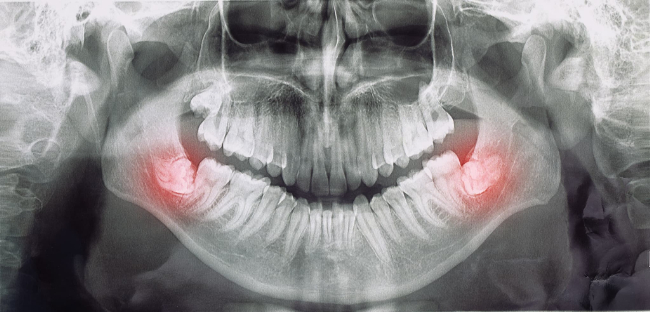

親知らずが生えている

親知らずは、必ず抜歯するわけではありません。

しかし、横向きや斜めに生えて周囲の歯に悪影響を与えている場合には、抜歯が必要となることがあります。横向きや斜めに生えていたり、位置がずれていたりすると、手前の奥歯に力がかかり、再び歯並びが乱れる可能性があるのです。

また、親知らずが虫歯や歯肉炎になっている場合も、ほかの歯への影響を考慮して抜歯することがあります。